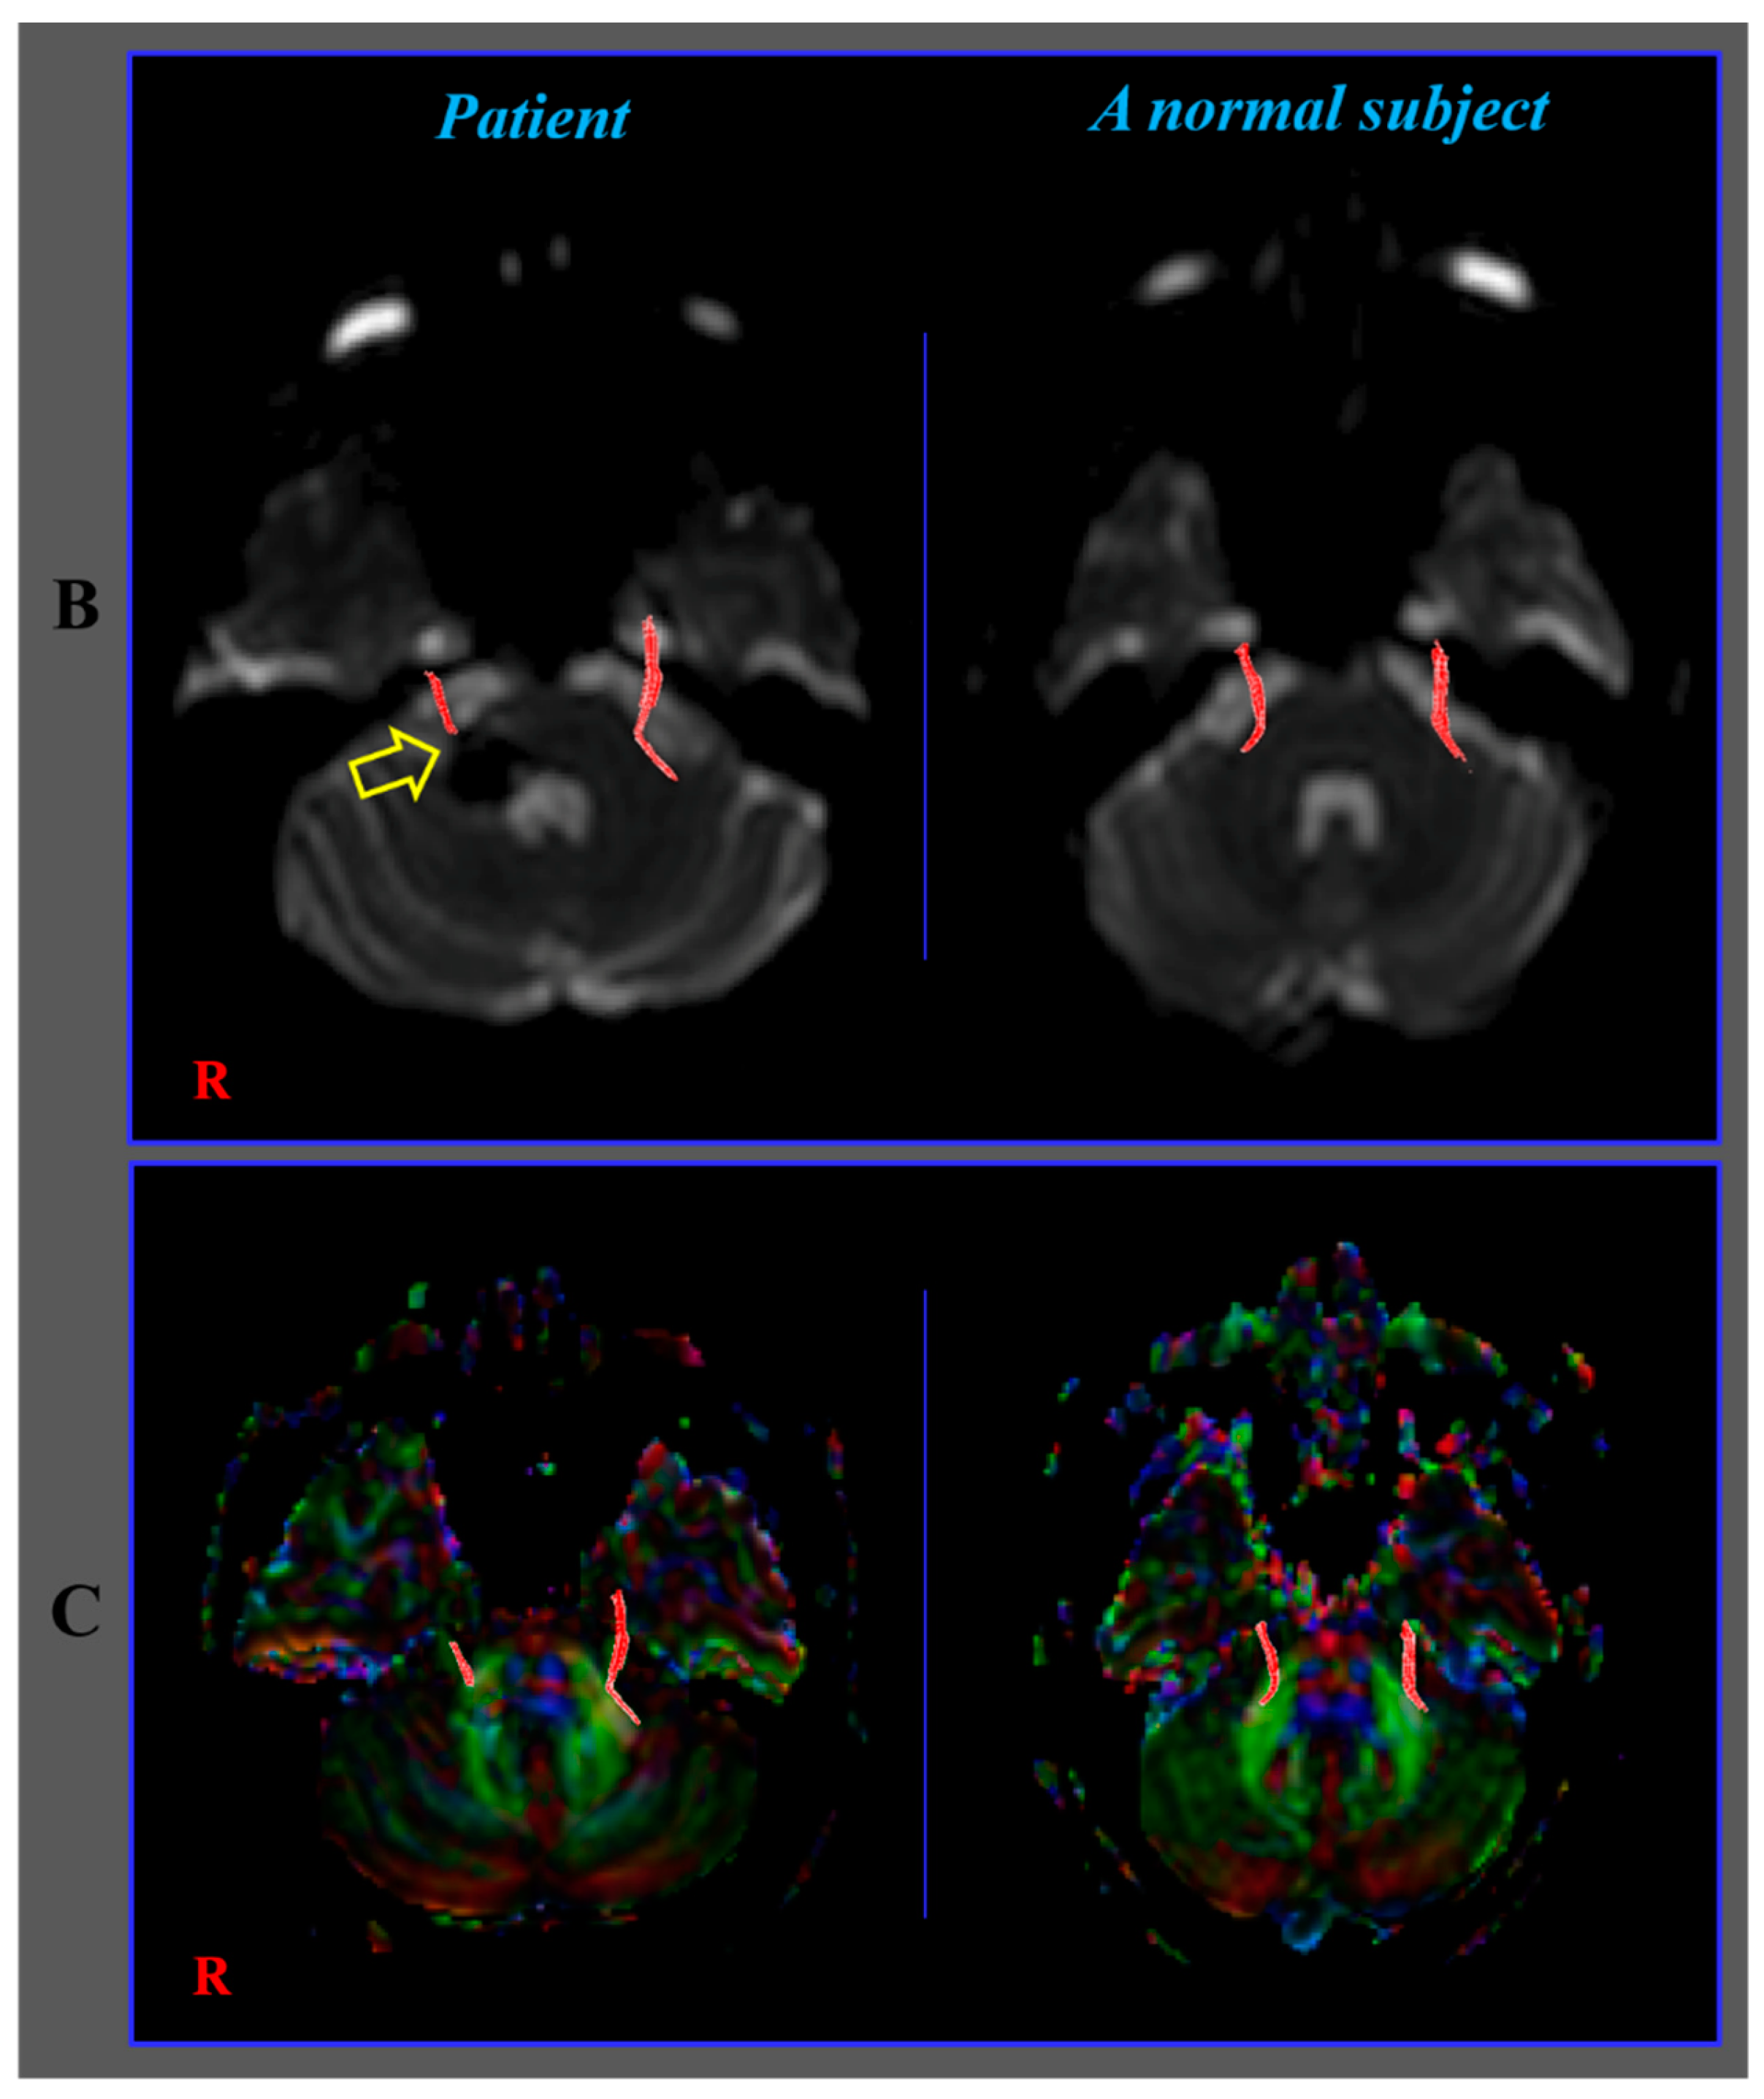

Diagnosis of the Trigeminal Nerve Injury in a Patient with Pontine Hemorrhage

Choi, E.B.; Seo, J.P.; Jang, S.H. Diagnosis of the Trigeminal Nerve Injury in a Patient with Pontine Hemorrhage. Diagnostics 2020, 10, 74. https://doi.org/10.3390/diagnostics10020074